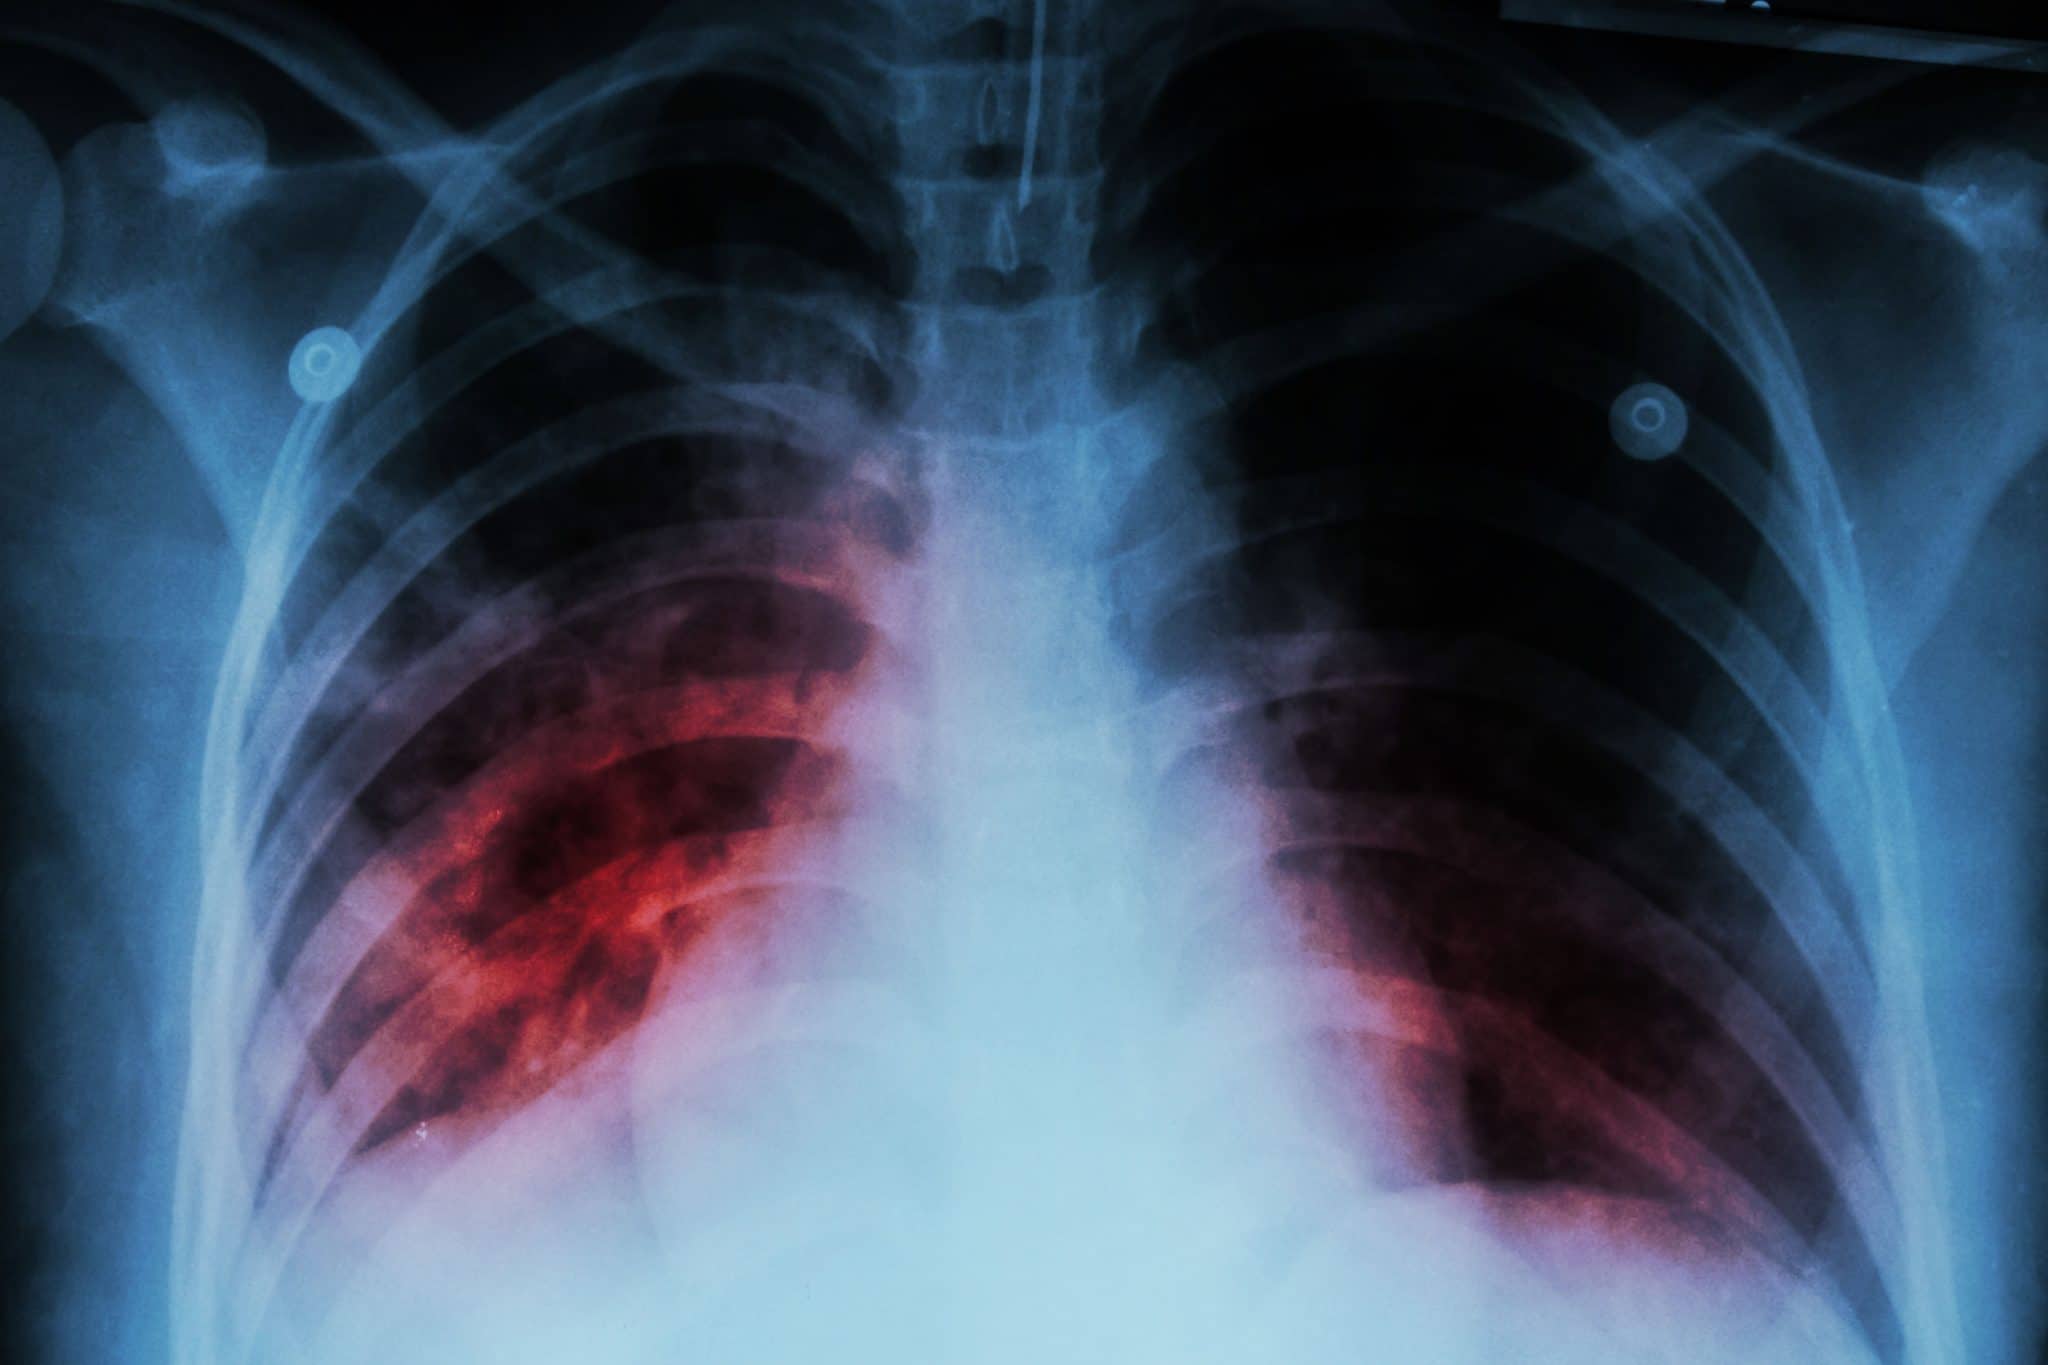

Back to top- Cough for more than two weeks.

- Can experience chest pain or pain while breathing

- Coughing up blood.